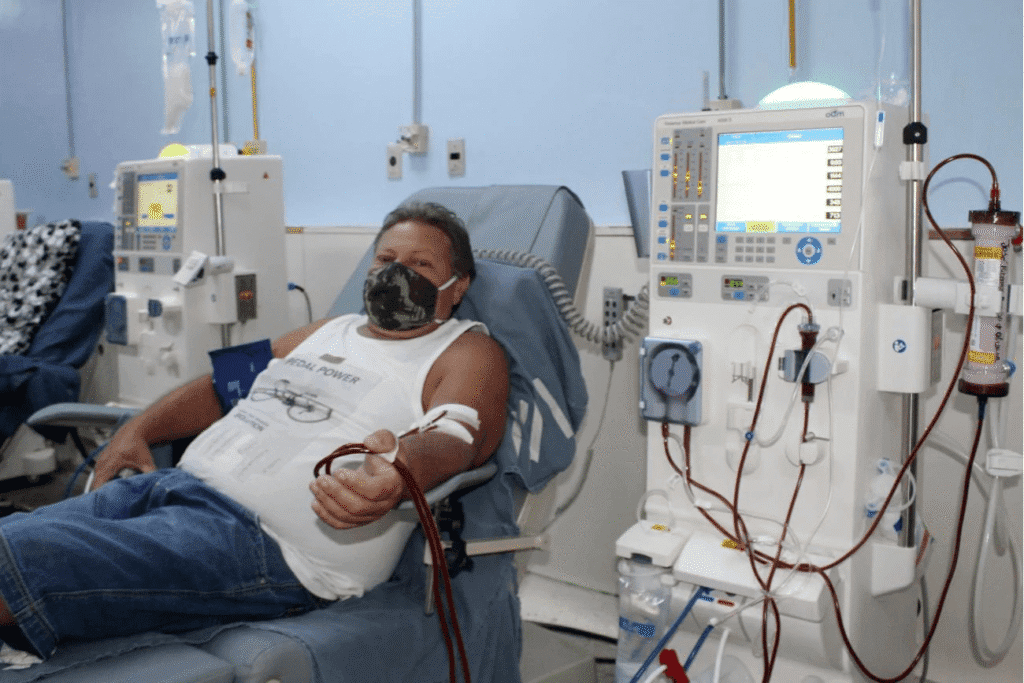

Manoel — o diabético que fez "tudo certo"... mas quase parou em uma máquina de hemodiálise

Seu Manoel, 64 anos, aposentado, morava no interior de Goiás. Diagnosticado com diabetes tipo 2 há mais de 22 anos por um endocrinologista que não irei falar o nome, sem histórico familiar.

Estava com a glicose em 290 mg/dL, sentia tonturas, visão embaçada, urinava 5x por noite e seus pés começaram a perder a sensibilidade.

O diagnóstico era: nefropatia diabética, que é uma complicação severa da diabetes. É a principal doença renal terminal em pacientes diabéticos, levando ao aumento da pressão arterial, presença de albumina na urina (albuminúria), causando a insuficiência renal. Tudo causado pelo uso contínuo de medicamentos pesados para a tipo 2.

Seus principais sintomas são: cansaço e fadiga, inchaço nas pernas e tornozelos, necessidade frequente de urinar e urina espumosa.

Mesmo assim, a glicose nunca ficava totalmente sob controle. Sempre ali, entre 240 e 290 mg/dL.

Bom, se ele não tivesse conhecido um outro caminho, na melhor das hipóteses estaria fazendo hemodiálise ou esperando por um transplante renal na fila do SUS.

Na terceira semana de internação, com a progressiva perda da função renal, ele quis procurar uma segunda opinião e veio desesperado até o meu consultório em São Paulo.